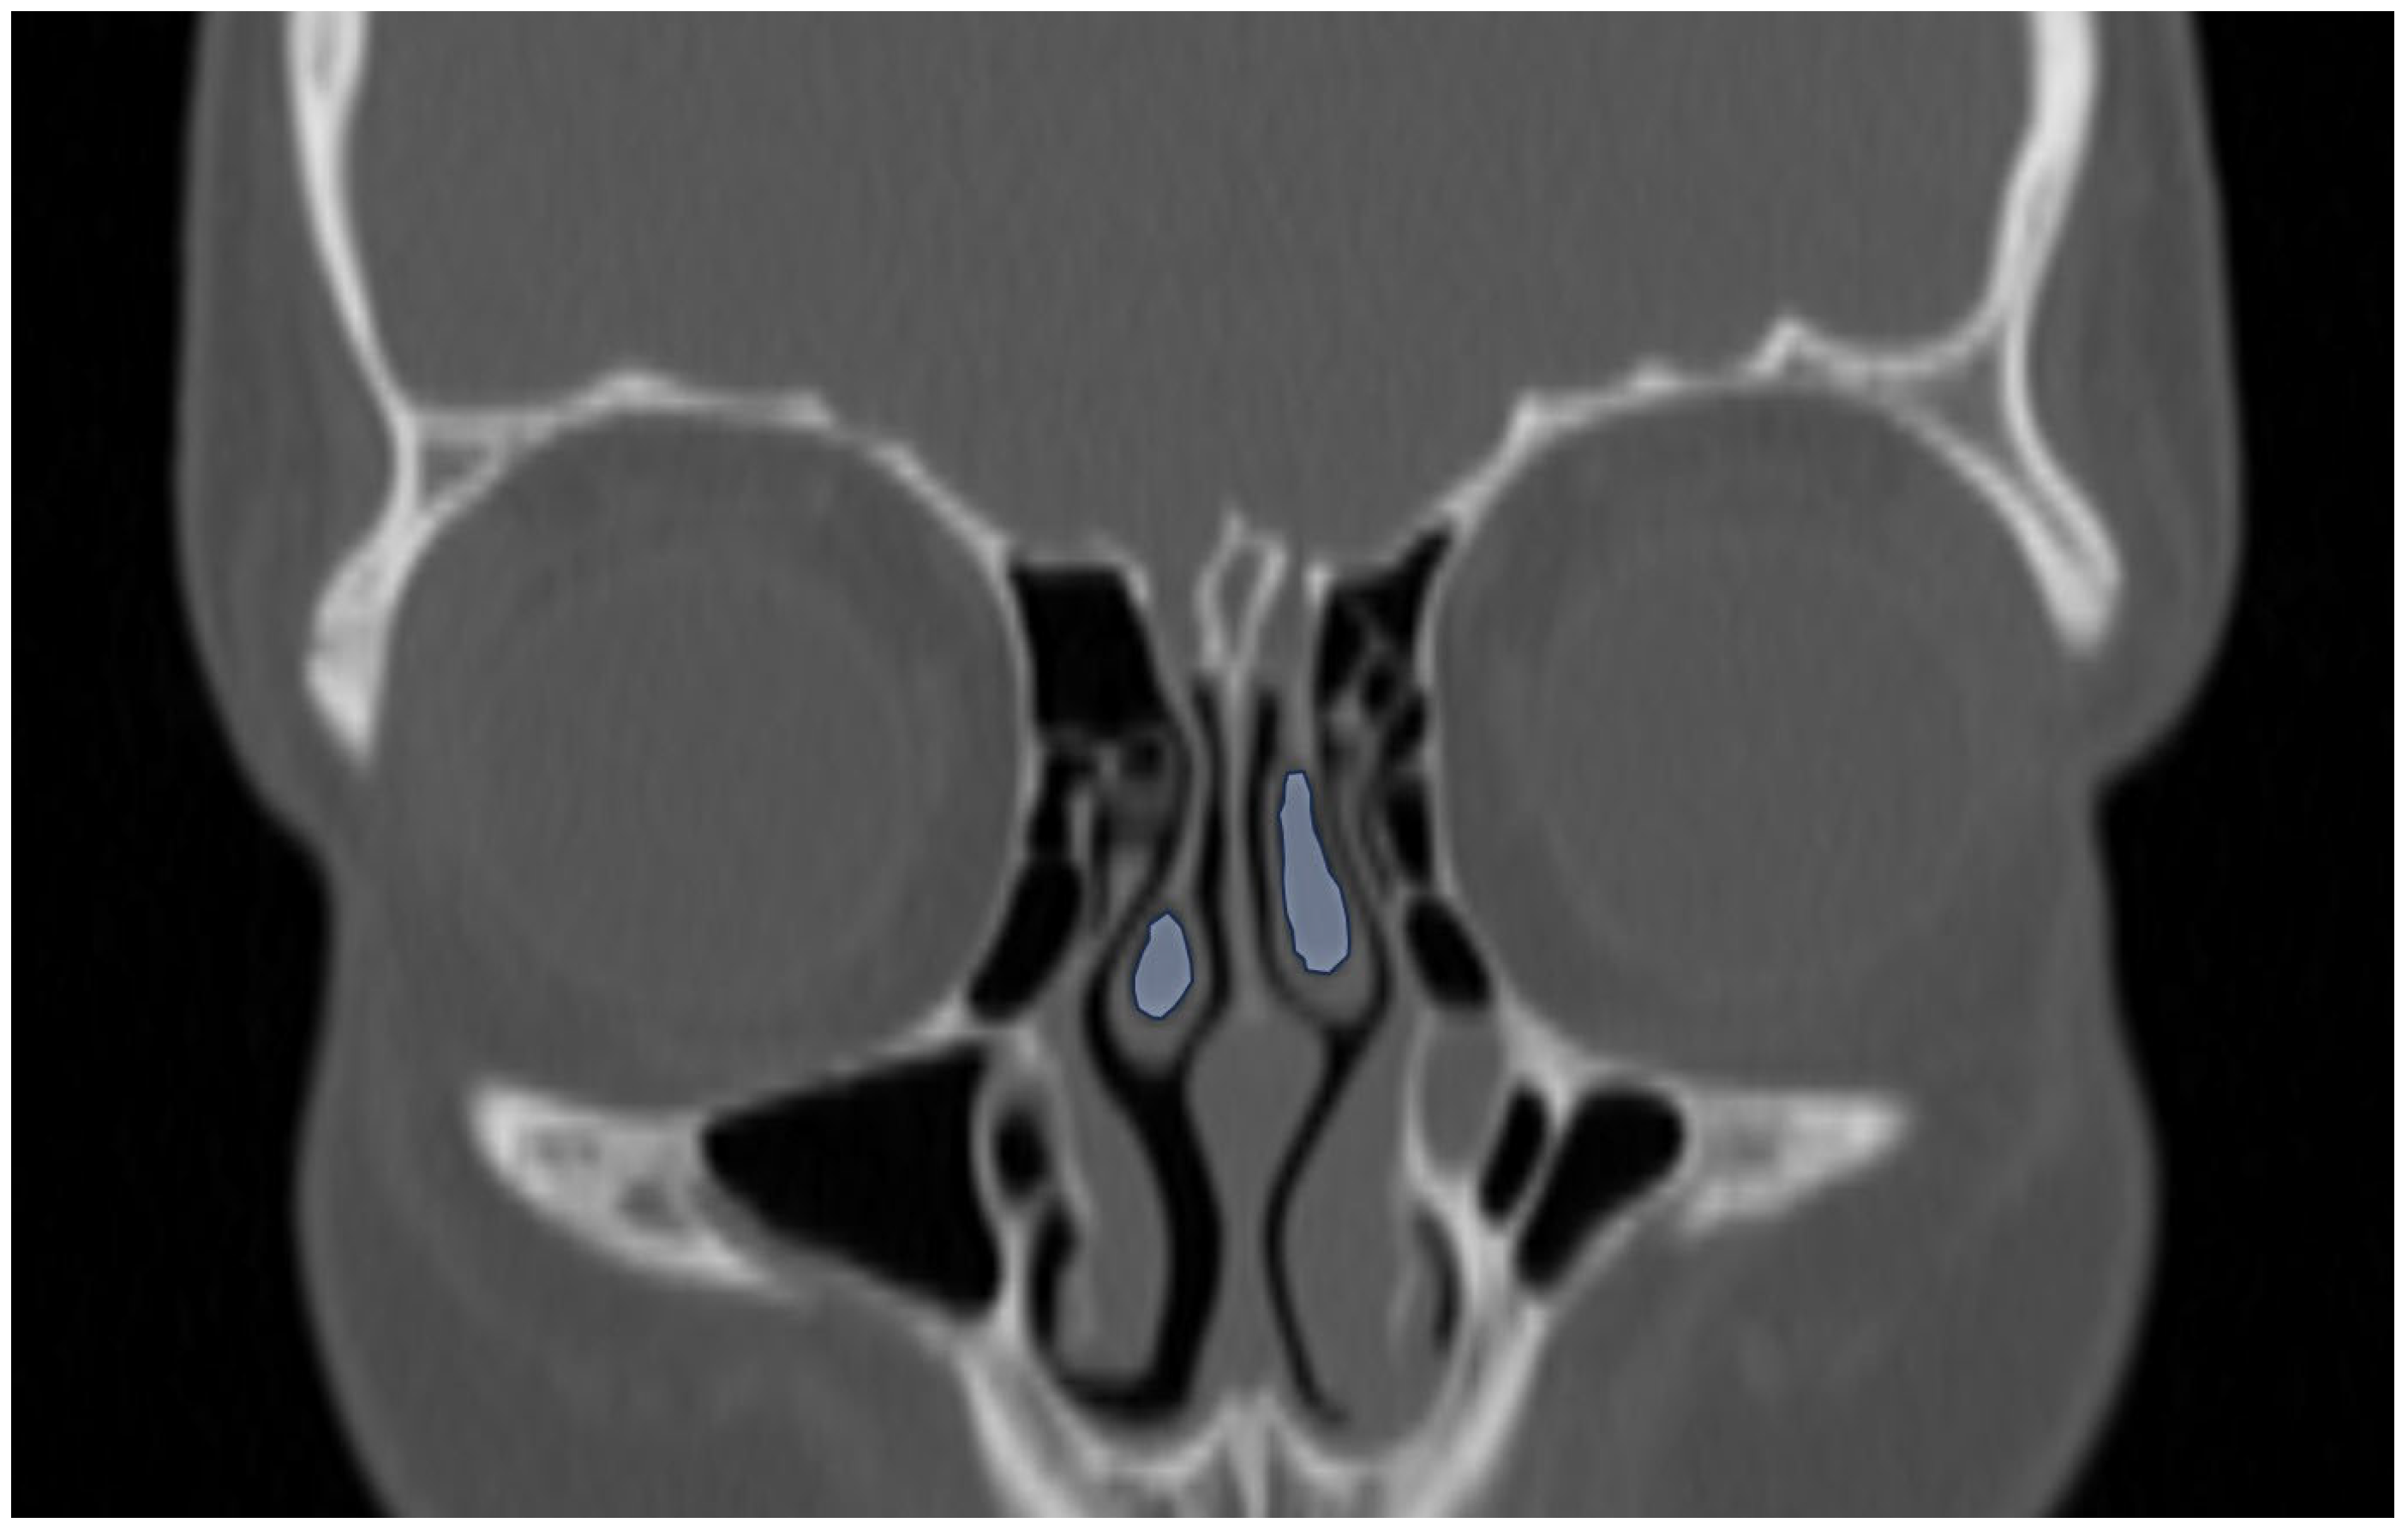

Additionally, the images were assessed for the presence of anatomic variants of the nasal cavity and PNS. Sinonasal variations were defined based on the European Position Paper on the Anatomical Terminology of the Internal Nose and Paranasal Sinuses [19]. According to this paper, the maxillary sinus is located between the orbital floor and alveolar process of the maxilla; the sphenoid sinus is the pneumatization of the sphenoid bone posterior to the rostrum; and the frontal sinus is defined as the pneumatization superior to a noticeable frontal beak [11,19]. The ANs are defined as the aeration of the protuberance on the lateral nasal wall, slightly anterior to the middle turbinate attachment (Figure 4). The Haller cell is an ethmoidal air cell, located below the orbital floor and lateral to a line parallel with the lamina papyracea (Figure 5). Onodi cell is the posteriorly located ethmoidal cell which develops just above and lateral to the sphenoid sinus (Figure 6). Concha bullosa is the pneumatization of the vertical segment of the middle turbinate (Figure 7) [19]. All anatomical variants were initially assessed by a single radiologist with four years of experience in maxillofacial CT imaging, who was blinded to patients’ demographic data, including age and sex. All assessments were done on a DICOM viewer (Medixant. RadiAnt DICOM Viewer [Software]. Version 2024.1. URL: https://www.radiantviewer.com (accessed on 1 November 2024)), after retrieval from the hospital PACS system to provide anonymized evaluation. The prevalence of each variant and the frequency of its bilaterality in each group were recorded. The evaluations were subsequently reviewed by a second radiologist with 11 years of experience. In cases of uncertainty regarding the presence of anatomical variations, a consensus decision was reached in consultation with a third radiologist with 13 years of experience.

Figure 7.

Coronal reformatted CT image of a 12-year-old boy demonstrating bilateral concha bullosa in the middle turbinate (blue areas).